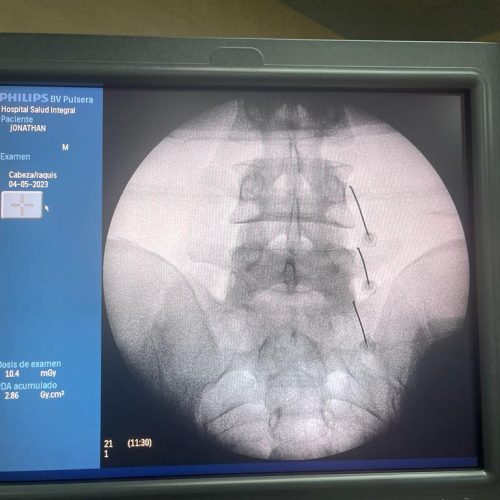

Fusión Vertebral (Cervical o Lumbosacra)

¿Qué es?

Es un procedimiento quirúrgico que busca estabilizar la columna vertebral uniendo de forma permanente dos o más vértebras. Se utilizan tornillos, barras y, en ocasiones, una caja intersomática con injerto óseo, para que las vértebras se fusionen en una sola unidad sólida.

¿Cuándo se indica?

- Espondilolistesis (desplazamiento vertebral)

- Inestabilidad vertebral causada por degeneración

- Fracturas vertebrales traumáticas

- Enfermedades degenerativas del disco

- Deformidades como escoliosis o cifosis

- Cirugías previas fallidas

¿Qué se logra?

- Estabilidad de la columna

- Reducción del dolor por movimiento excesivo

- Prevención de daño neurológico progresivo